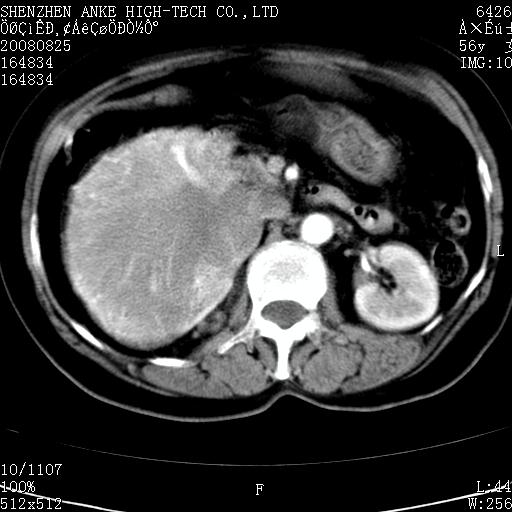

患者,女性,56岁,腰痛3年,查:右腹部约8x10cm肿块,固定,无压痛;8月23日在外院做了平扫,发现右肾巨大肿块(外院具体诊断不祥);今天在我院做了静脉肾盂造影,示:右肾明显增大,分泌功能明显减弱。

右肾癌可能大。

右肾癌

右肾癌可能性大.

右肾占位、癌可能性大。

支持右巨大肾癌。

1)考虑右肾癌并右肾静脉瘤栓形成。2)脂肪肝。

右肾癌可能性大。

右肾癌性变。

考虑右肾癌可能性。